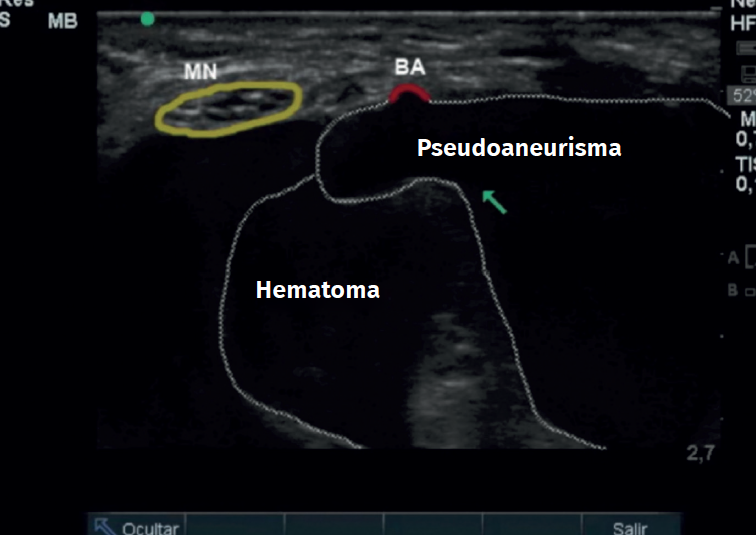

Se completa el estudio con una ecografía (Figura 2), observándose la presencia de un pseudoaneurisma en la arteria braquial con flujo arterial positivo. Y con un electromiograma que informa de una lesión aguda incompleta del nervio mediano.